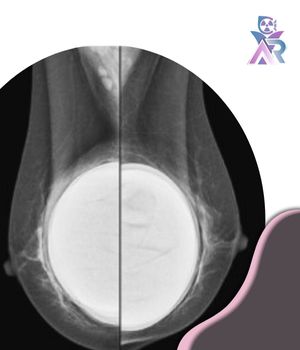

پروتز سینه معمولاً از جنس سیلیکون یا سالین ساخته می‌شود و ممکن است در زیر بافت سینه یا زیر عضله سینه‌ای بزرگ قرار گیرد. نوع و محل قرارگیری ایمپلنت نقش مهمی در نحوه انجام ماموگرافی دارد زیرا هر کدام می‌تواند میزان دیده شدن بافت طبیعی پستان را تحت تأثیر قرار دهد. وجود پروتز می‌تواند تا حدی مانع از مشاهده کامل بافت‌های عمقی در تصاویر شود به‌خصوص زمانی که ایمپلنت در لایه سطحی‌تر قرار گرفته باشد. به همین دلیل تکنسین رادیولوژی باید از روش‌های تخصصی برای جابه‌جایی پروتز و تصویربرداری دقیق ‌تر استفاده کند.

یکی از مهم‌ترین روش‌های تصویربرداری در این شرایط تکنیک جابه‌جایی ایمپلنت است. در این روش تکنسین با حرکات کنترل‌شده ایمپلنت را به سمت دیواره قفسه سینه فشرده می‌کند تا از میدان دید اشعه خارج شود و در همان زمان بافت طبیعی سینه به سمت جلو کشیده می‌شود. این کار باعث می‌شود بخش بیشتری از بافت واقعی پستان در تصاویر قابل مشاهده باشد و احتمال پنهان ماندن ضایعات یا توده‌های کوچک کاهش یابد.

روش های تکمیلی برای افزایش وضوح تصاویر

وجود پروتز ممکن است باعث کاهش وضوح و شفافیت در بخش‌هایی از بافت سینه شود زیرا سیلیکون یا محلول سالینی داخل ایمپلنت می‌تواند تا حدودی اشعه ایکس را جذب یا منحرف کند. در نتیجه برخی قسمت‌ها ممکن است در تصاویر اولیه به‌خوبی دیده نشوند. بنابراین پزشک باید تصاویر را با دقت بیشتری بررسی کرده و از دانش تخصصی خود برای تشخیص دقیق‌تر استفاده کند.

در چنین شرایطی معمولاً از تعداد بیشتری نما (۸ نما به‌جای ۴ نما) برای هر سینه استفاده می‌شود تا تمام بخش‌های بافت طبیعی سینه از زوایای مختلف تصویربرداری شوند.

علاوه بر این ممکن است از تصویربرداری دیجیتال سه‌بعدی (توموسنتز) نیز کمک گرفته شود تا تصاویر لایه‌لایه از بافت پستان ایجاد شده و تشخیص نواحی مشکوک آسان ‌تر گردد.